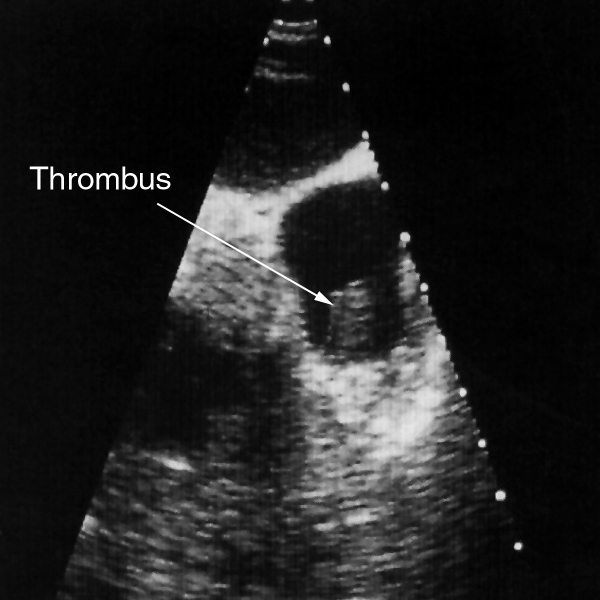

Man kann bei der TEE-Untersuchungen verschiedene Dinge sehen, z.B. entzündliche Auflagerungen auf den Herzklappen (Abb. 5), Löcher in Trennwänden innerhalb des Herzens bei angeborenen Herzfehlern (Abb. 6),

Thrombus rechter Vorhof

Abb. 7 Abb. 8

Gerinnsel in den Herzvor- oder -hauptkammern (Abb. 7) oder Vergrößerung der verschiedenen Herzhöhlen (Abb. 8) finden.